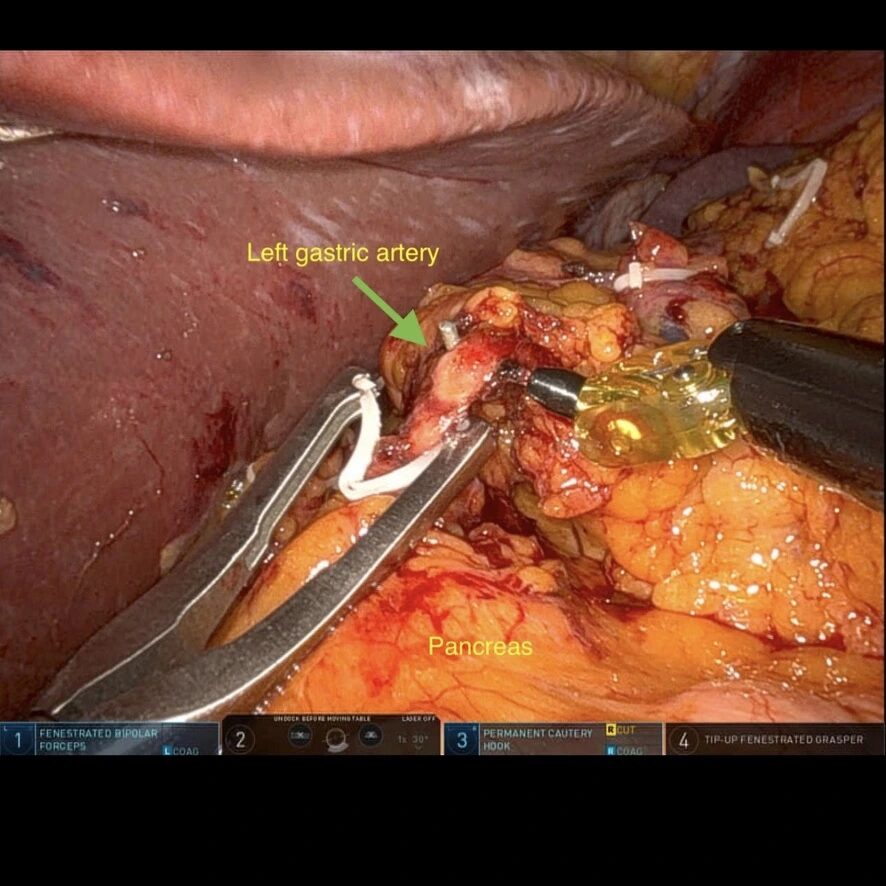

- disecția / limfadenectomia trunchiului celiac si a arterei gastrice stângi cu pregatirea pentru cliparea arterei gastrice;